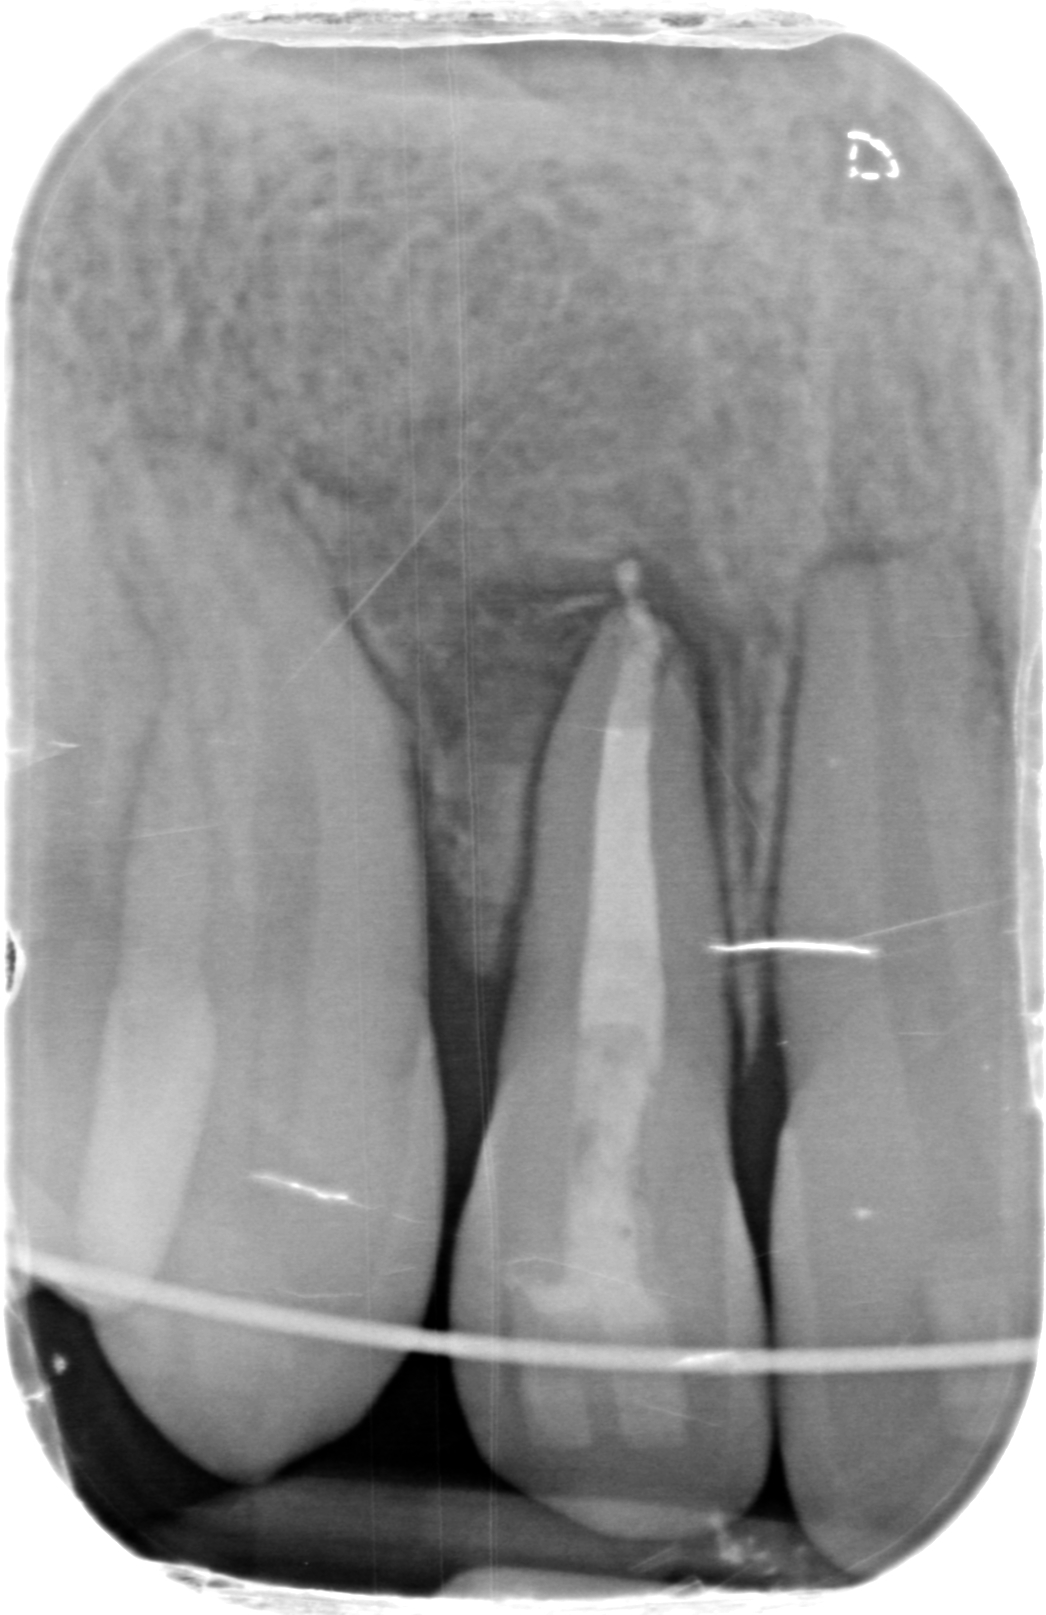

La Endodoncia es la especialidad que permite conservar el diente en boca cuando la patología pulpar del diente es ya irreversible.

Durante una endodoncia, vulgarmente conocida como “matar el nervio”, lo que hacemos es eliminar el tejido pulpar (el nervio) enfermo y conformar y desinfectar todo el sistema de conductos radiculares, para luego rellenar y sellar esos conductos de un material termoplástico. A continuación hay que Reconstruir la corona mediante técnicas adhesivas, bien con composite o si la reconstrucción es muy grande, recurrimos a la Porcelana como mejor material para restituir la integridad funcional y anatómica perdida.